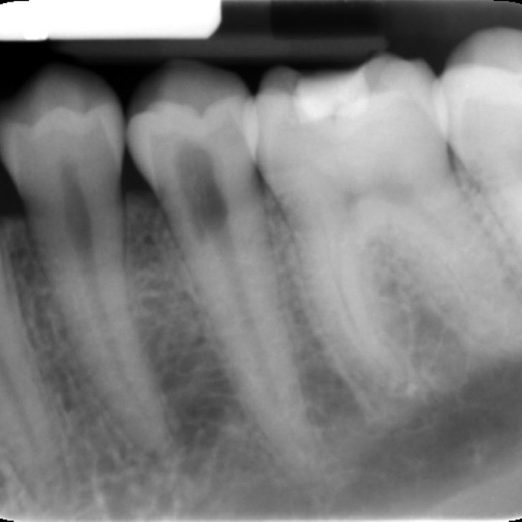

External cervical resorption typically presents as an asymmetrical radiolucency with irregular borders (Figure 4).

The outline of the root canal is visible through the lesion indicating the resorption is on the external aspect of the tooth.

The lesion may appear cloudier or mottled if it has progressed into a more reparative phase.

In addition to this, not all external cervical resorption lesions follow the ‘typical’ radiographic appearance mentioned above (Figure 5). A CBCT provides crucial information to obtain successful outcome.

Figure 5: From the PA radiograph LR5 has the classical appearance of internal resorption.

However, the CBCT scan shows the resorption is external cervical resorption.